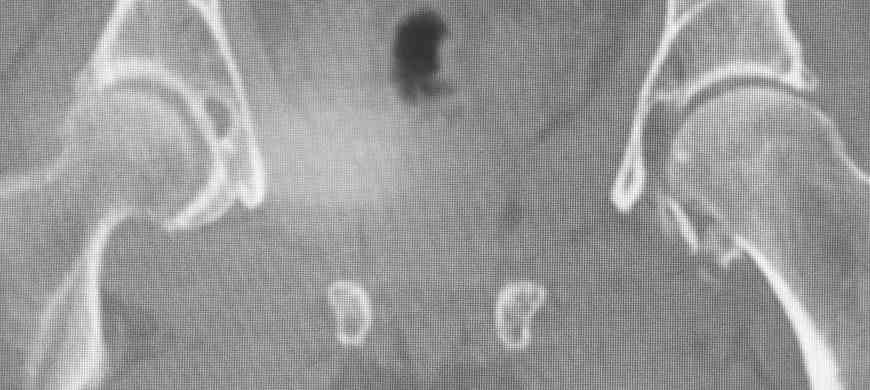

Pipkin II

Стоило ли заниматься остеосинтезом в этом случае?

Мужчина, 50 лет, активный, падение с высоты. При поступлении вправление вывиха, других повреждений нет Без значимой сопутствующей патологии, не курит. Стоило ли выполнять остеосинтез при таком оскольчатом переломе или сразу пойти на ТНА?